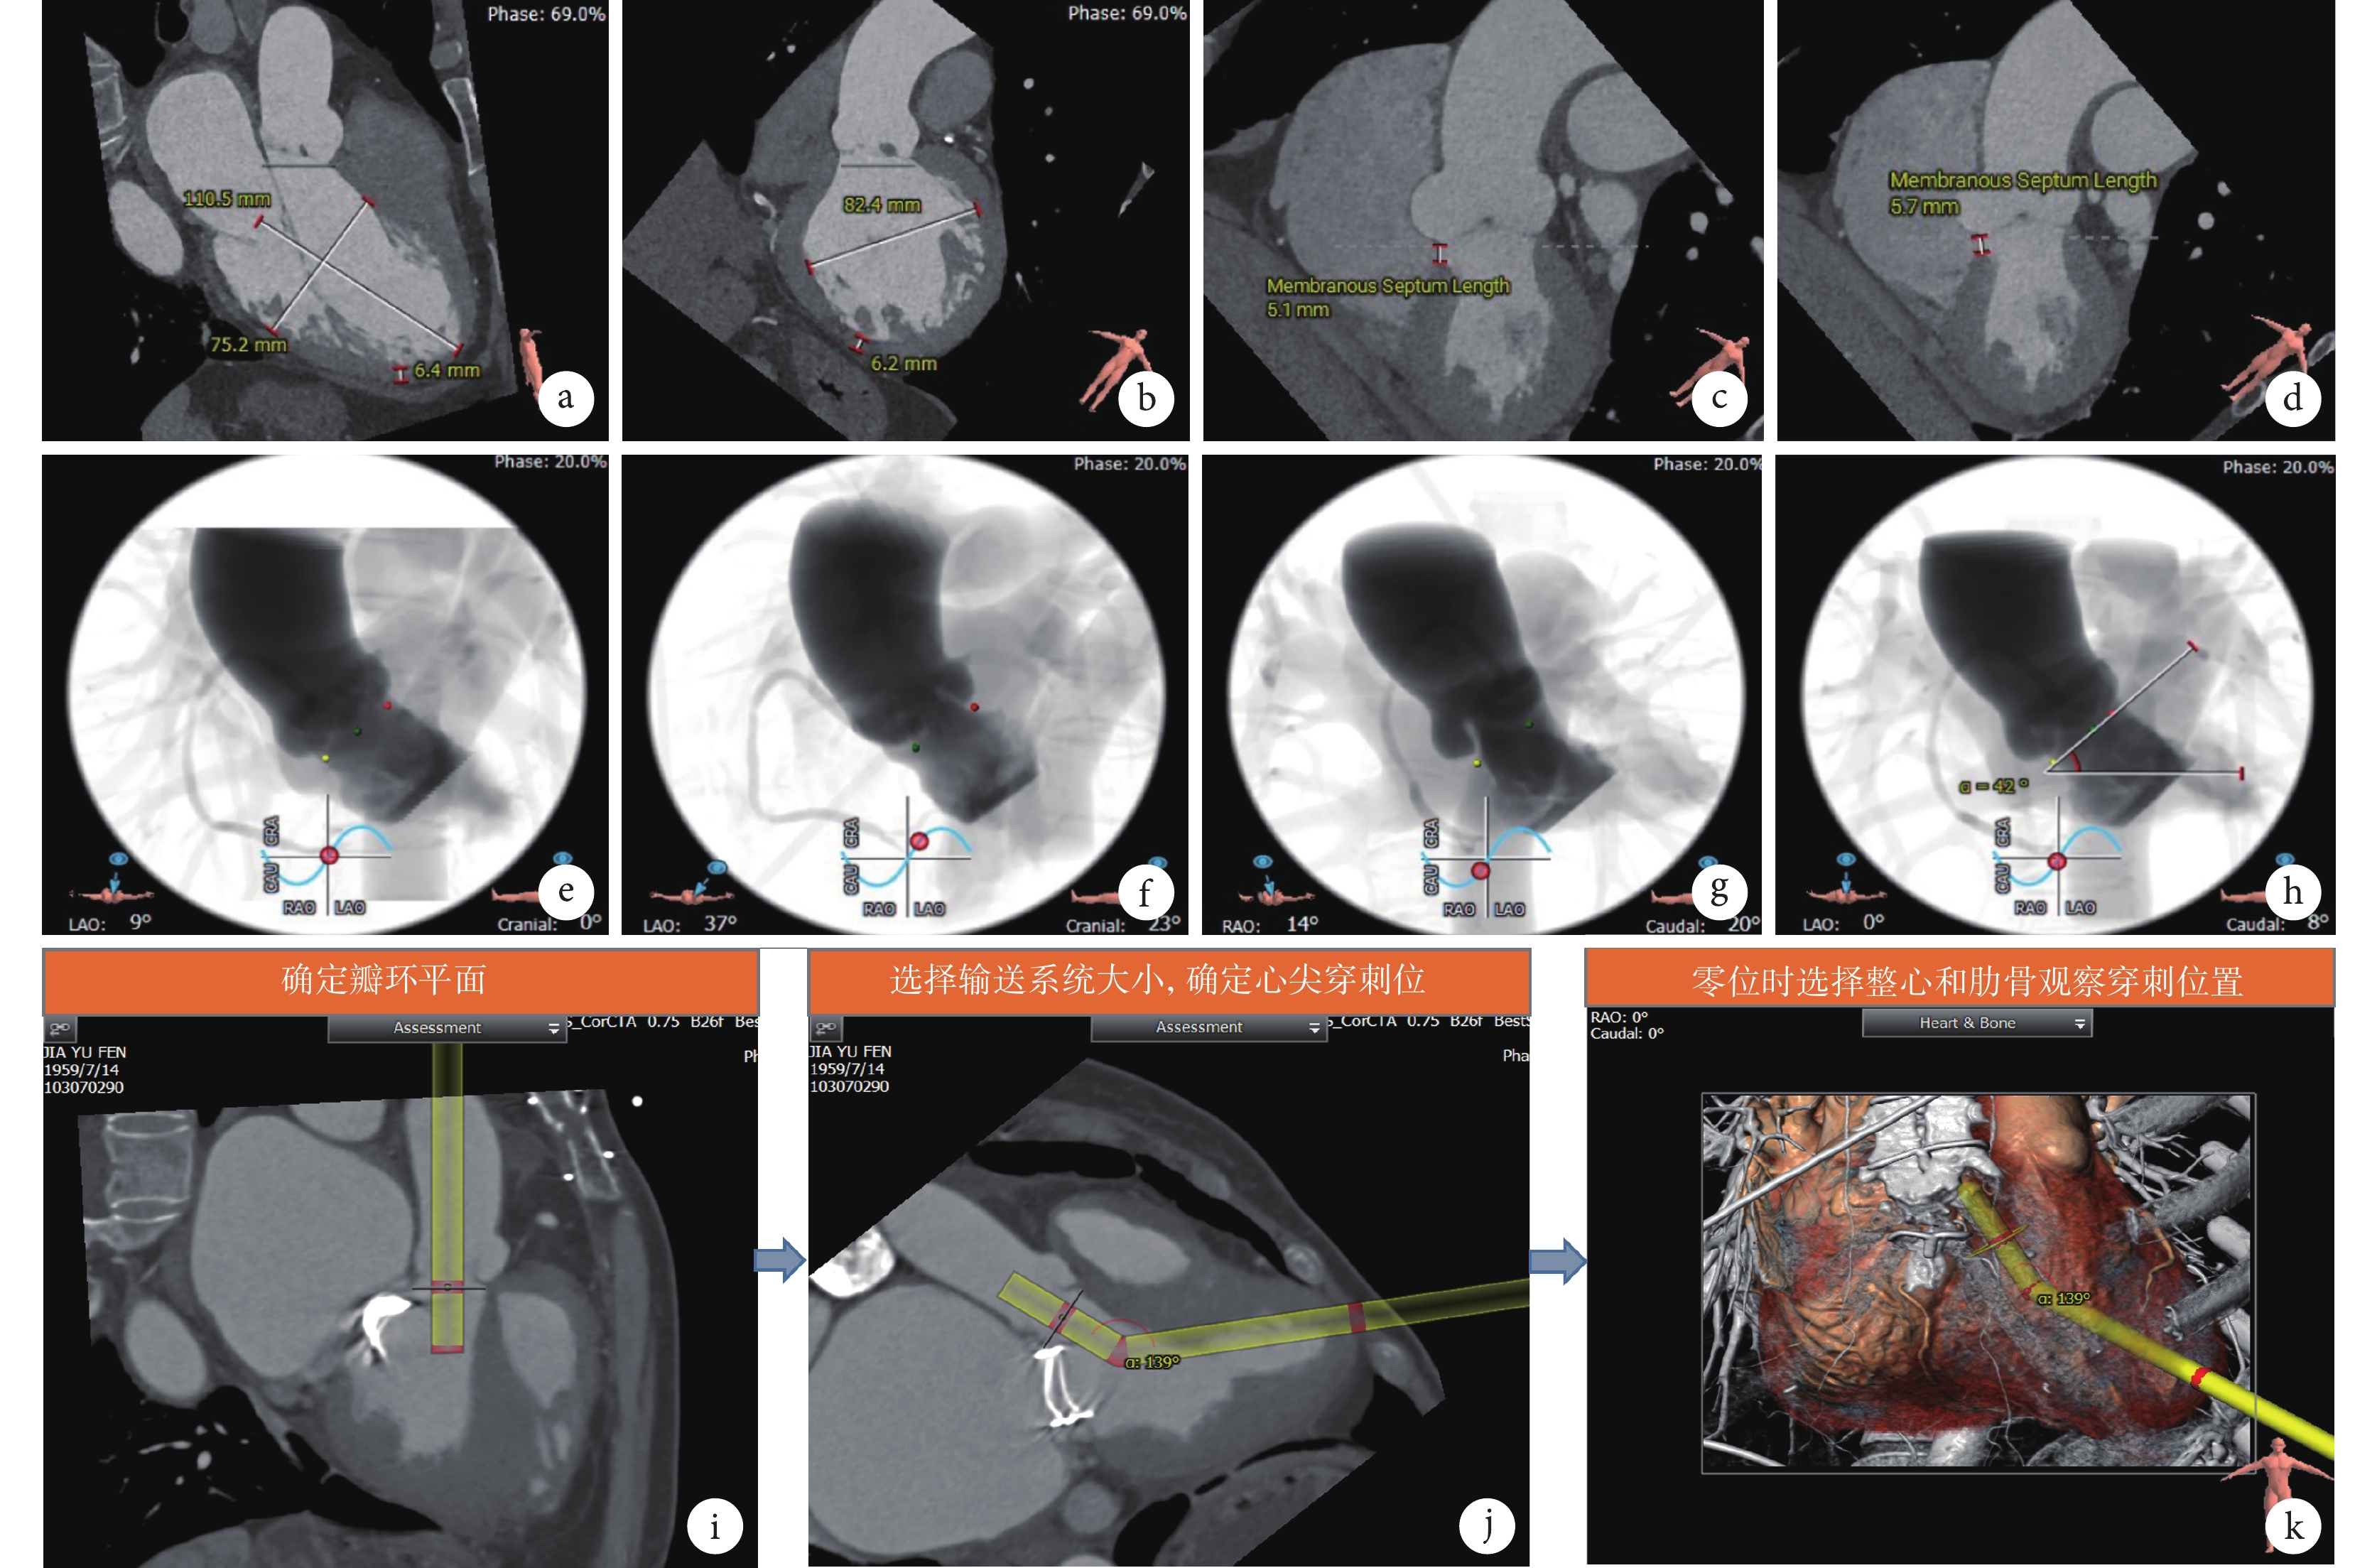

通過幾次會議溝通,專家一致認為,經心尖入路TAVR除對主動脈根部進行仔細評估外,還需對經心尖入路相關的心室大小、室壁厚度、室間隔膜部高度、瓣環水平面夾角、術中投照角度、經心尖入路夾角進行分析評估(圖5)。

a~b:心室大小測量;c~d:室間隔膜部高度測量;e~g:術中投照角度計算;h:瓣環水平面加夾角測量;i~k:經心尖入路夾角確定